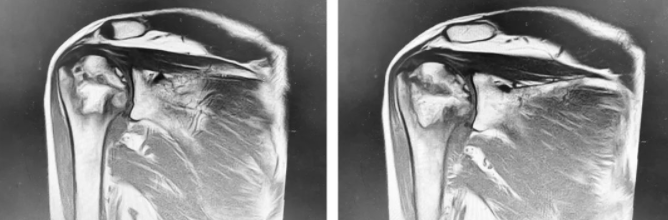

术前

入院后,经系统检查,王师傅被确诊为“右肱骨头无菌性坏死”(Cruess分期 Ⅲ期)、右肩袖损伤。随后,经过详细的病情讨论及术前准备, 张传开、陈强、杨沛霖、徐猛手术团队为王师傅进行了反向全肩关节置换术。手术进行的很顺利,王师傅现已在医生的指导下进行康复锻炼,肩关节功能恢复指日可待。